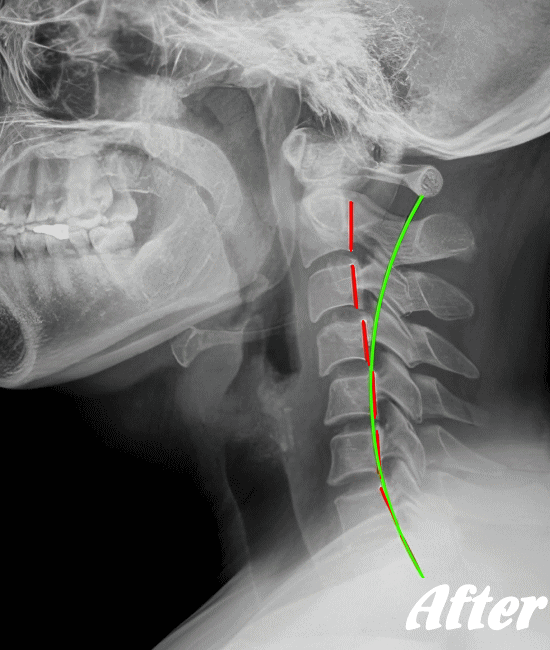

HALOカイロプラクティック☆平和島整体院では、骨盤から背骨全体(腰椎、胸椎、頸椎)を調整し、肩甲骨の動きを柔軟にし、首周りの筋肉をゆるめ、頚椎の骨と骨との間隔を広げ、動きを滑らかにして、首の負担を軽減させながらバランスを整える施術を行います。

頚椎症は、速効矯正・即効施術の【体の整体】の適応になります。